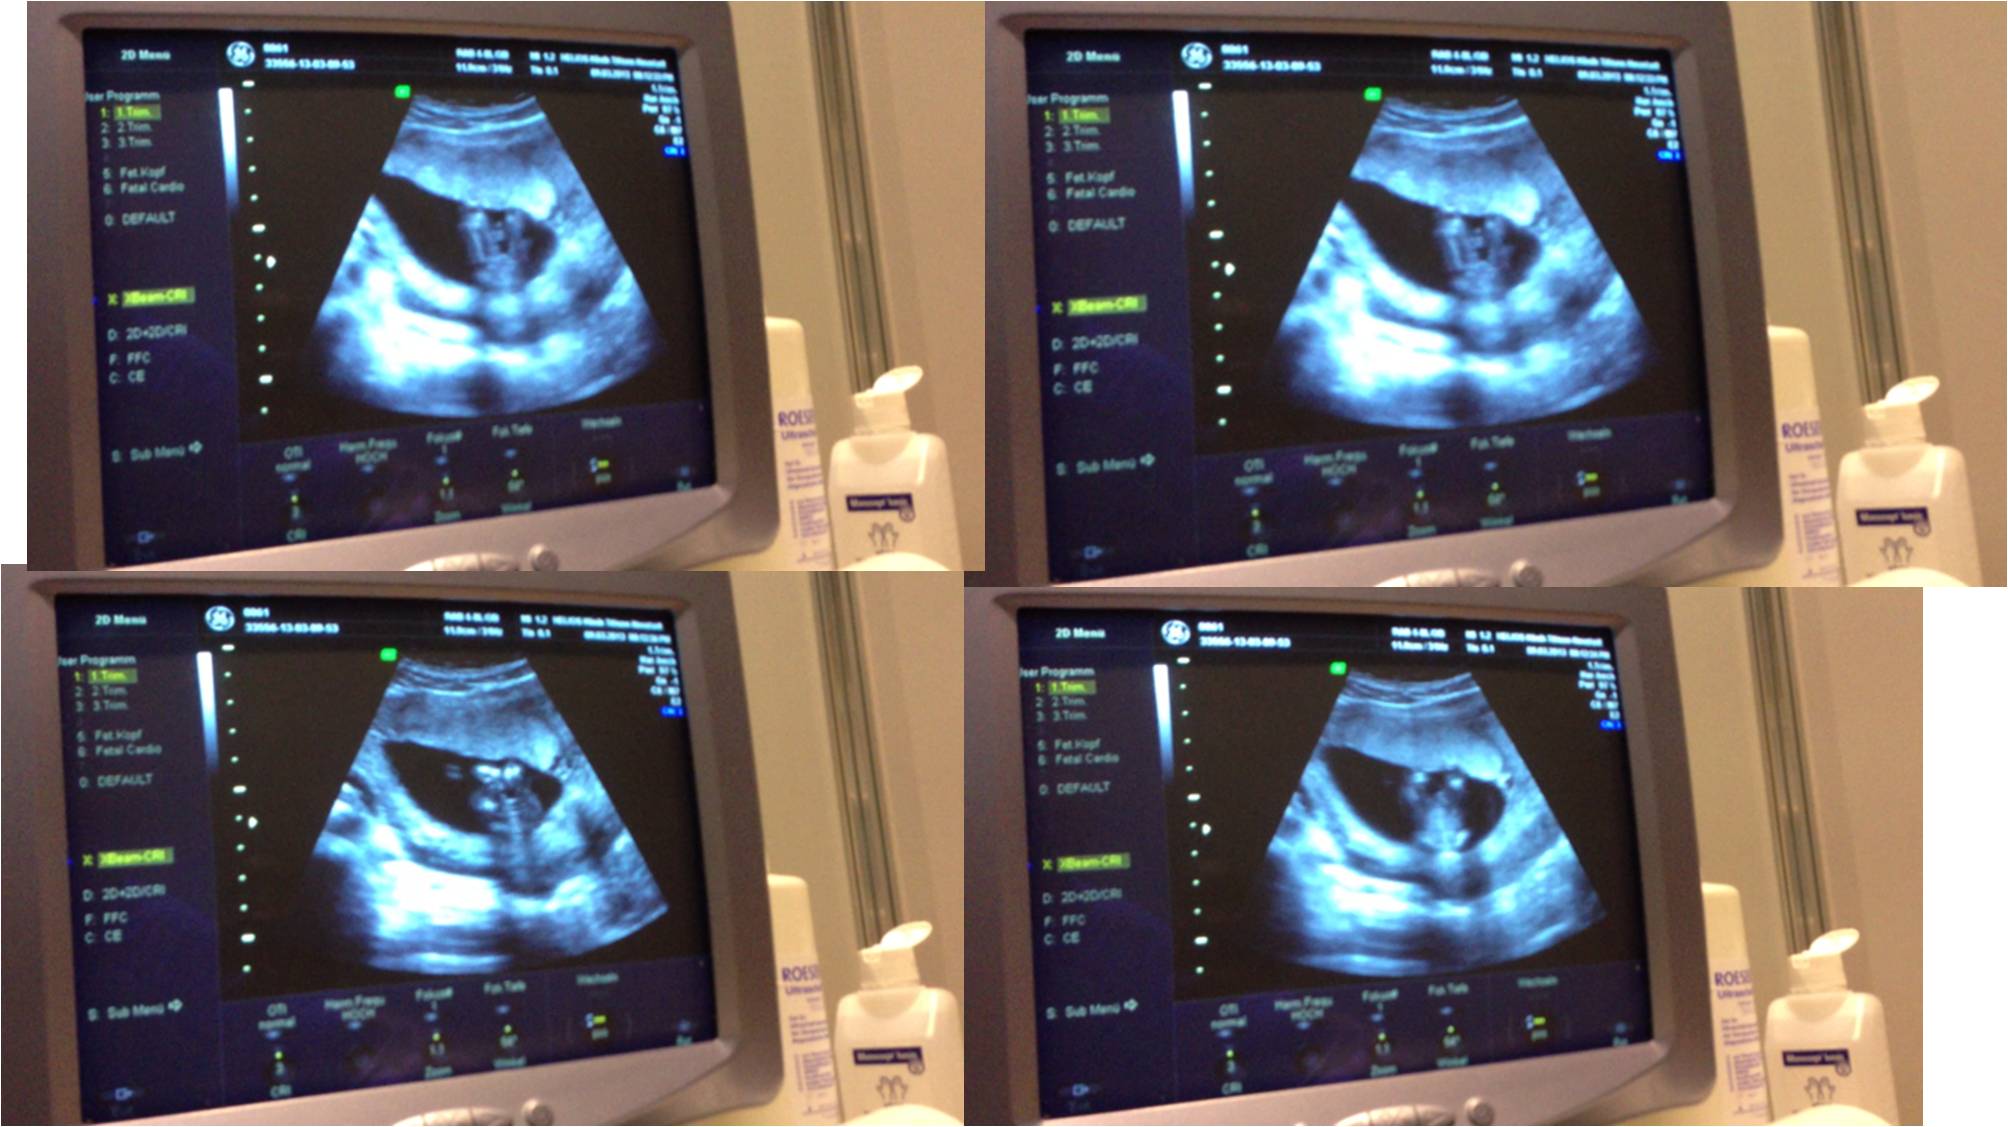

Hi again! Here are my 16 weeks potty shots !!!! PLEASE HELP ME! What do you see??? BOY ORE GIRL :-))) Thank you sooo much! All this gender situation drives me crazy :-( Greetings and good luck everyone ! Ps. The doctor really confused me :/Attachment 9559

Attachment 9560 Attachment 9560